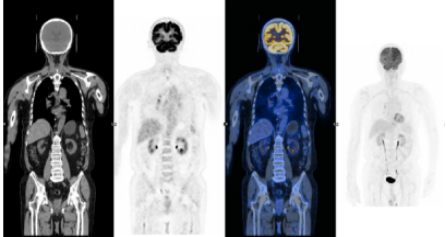

患者使用第3周期塞利尼索联合地西他滨和R-Gemoxd方案进行化疗后,行T细胞采集,拟进行CAR-T细胞治疗,随后再次使用1个疗程塞利尼索联合地西他滨和R-Gemoxd方案化疗,复查PET/CT显示:持续CR。回输CAR-T细胞后复查PET/CT显示:持续CR。

上图:CAR-T治疗前PET/CT显示:CR

下图:CAR-T回输后1月复查PET/CT显示:CR